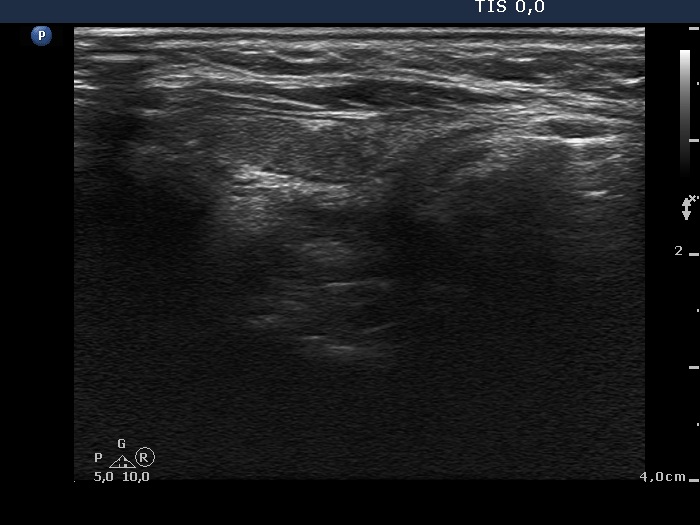

Ultrasonography. The right thyroid was moderately hypoechogenic without any circumscribed lesions. The left thyroid was removed. There were several enlarged lymph nodes in the right submandibular area. The largest one presented two discrete, more hypoechogenic intranodal lesions and a regular hilum.